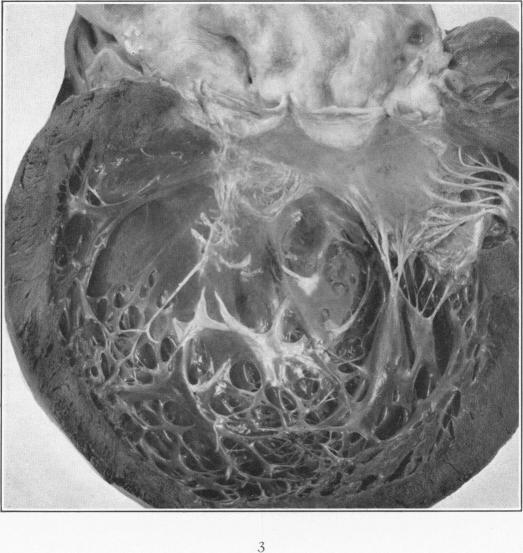

Endocardial Pockets.

Am J Pathol. 1930 Nov;6(6):733-748.5.